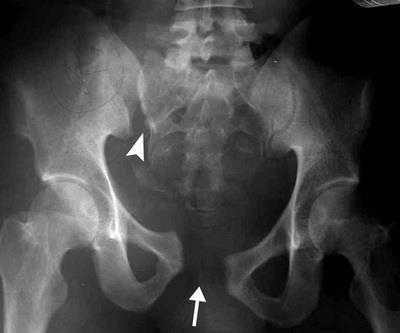

Рентгенограмма нестабильного повреждения таза с разрывом лонного симфиза (стрелка) и крестцово-подвздошного сочленения (треугольная стрелка).